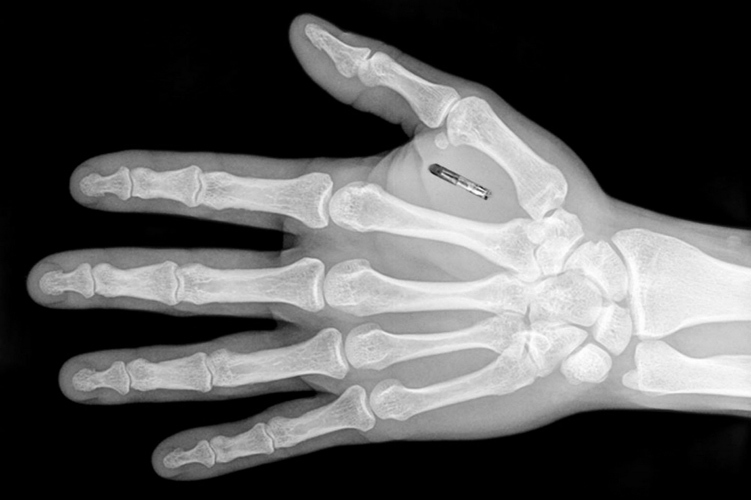

Сейчас чипирование выглядит так: чип размером с рисовое зерно с 1 килобайтом ваших данных вводится вам под кожу с помощью специального шприца между большим и указательным пальцами. Процедура занимает несколько минут и стоит около 180 долларов. За пять лет работы Biohax International имплантировала более 4000 чипов.

© Three Square Market Тодд Вестби, CEO Three Square Market, открывает дверь в офис компании с помощью чипа Ясно, что это первые шаги. В сентябре 2017 года Three Square Market запустила ответвление Three Square Chip, занятое разработкой коммерческих микрочипов-имплантатов, учитывающих особенности здоровья каждого человека. В планах Biohax — размещение в чипах паспортных и медицинских данных. В этом месяце технологический стартап DSruptive собирается представить в Стокгольме «потребительский имплантат следующего поколения». Устройство будет включать в себя два килобайта памяти — вдвое больше, чем у сегодняшних имплантатов, — и ряд новых функций, включая появление светодиода, мигающего, когда кто-то посторонний пытается прочитать ваш чип или получить к нему доступ.